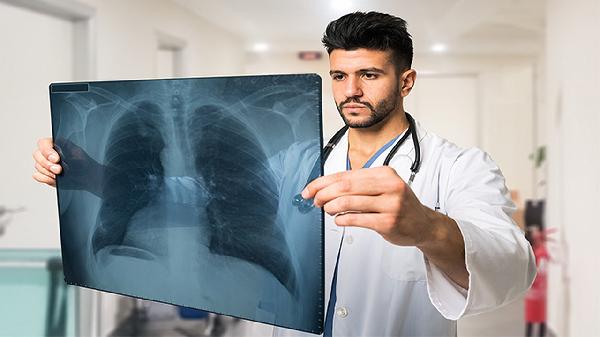

支原体肺炎用什么药效果最好

支原体肺炎可遵医嘱使用阿奇霉素片、盐酸多西环素片、左氧氟沙星片、罗红霉素胶囊、克拉霉素片等药物。支原体肺炎是由肺炎支原体感染引起的呼吸道疾病,主要表现为发热、咳嗽、咽痛等症状,需根据患者年龄、药物过敏史及病情严重程度选择合适药物。

支原体肺炎患者应保证充足休息,每日饮水1500-2000毫升以稀释呼吸道分泌物。保持室内空气流通,湿度维持在50%-60%。饮食选择易消化的高蛋白食物如鸡蛋羹、鱼肉粥,避免辛辣刺激。咳嗽剧烈时可饮用蜂蜜水缓解,儿童需家长监督服药全程。如出现持续高热、呼吸困难或精神萎靡应及时复诊,治疗期间避免前往人群密集场所。